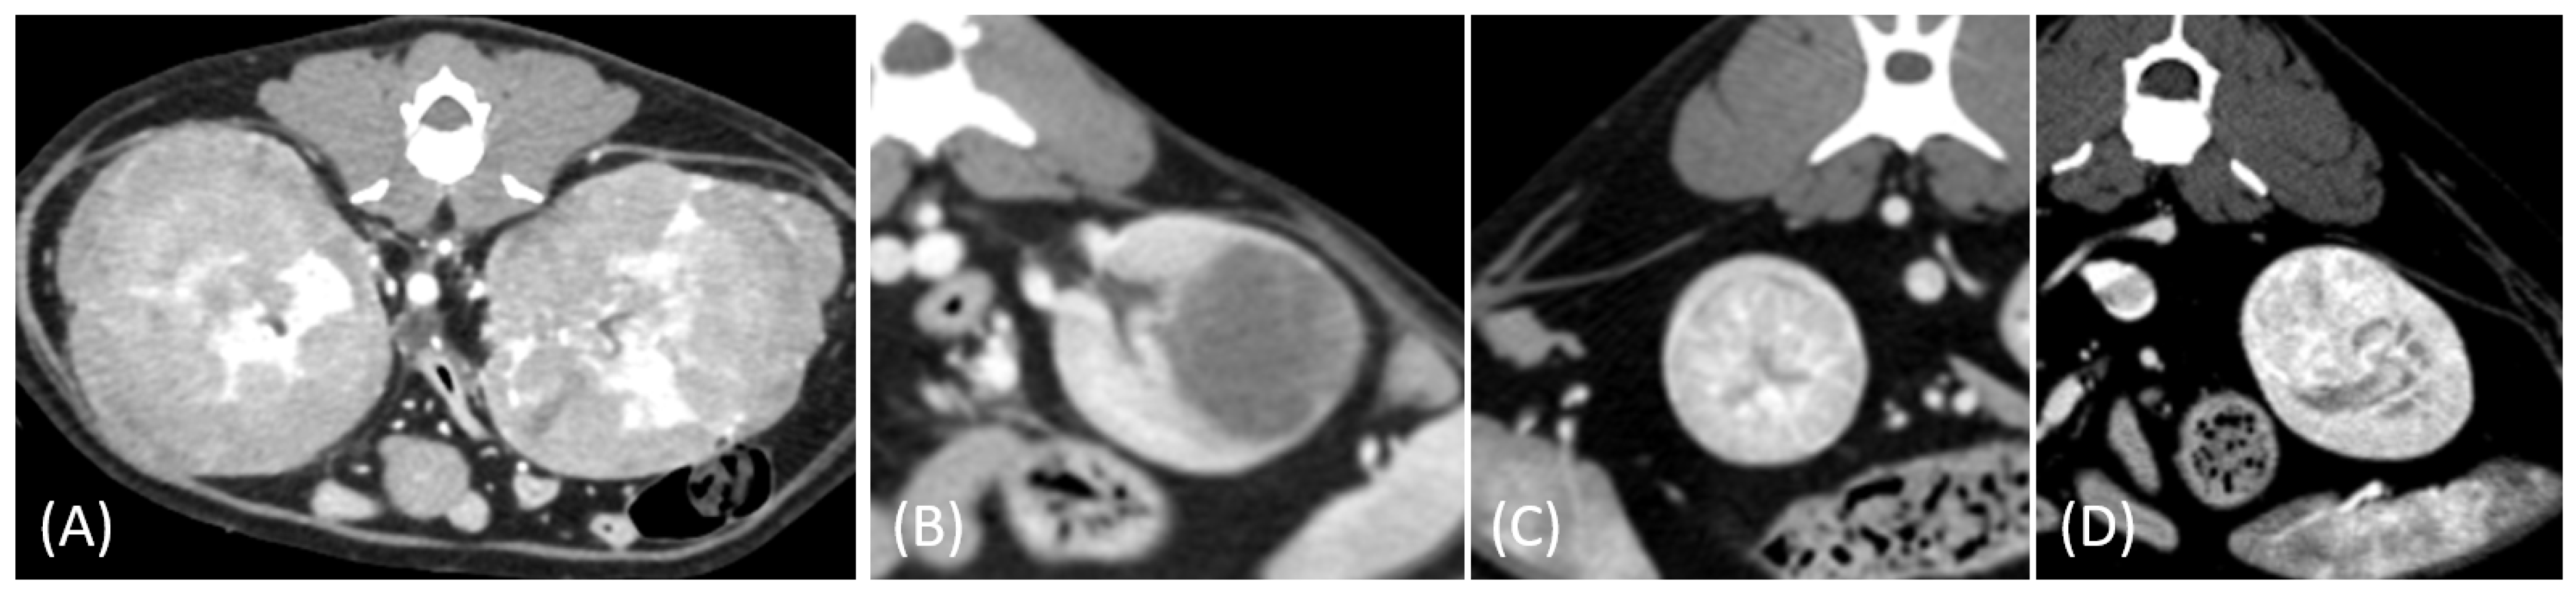

Figure 4.

(A) Pre-contrast, (B) corticomedullary phase, (C) nephrographic phase, and (D) delayed nephrographic/early excretory phase contrast-enhanced computed tomography (CT) images of a renal cell carcinoma. The tumors are bilateral, predominantly demonstrating an expansile growth pattern. They appear relatively homogeneous and hypoattenuating, resembling the imaging characteristics of multiple lymphoma masses. Progressive enhancement is observed throughout the phases. These findings highlight the overlapping imaging features between renal cell carcinoma (RCC) and lymphoma in certain cases.

In contrast, one RCC case in our study presented with multiple bilateral renal masses displaying relatively low contrast enhancement, posing a diagnostic challenge in differentiating it from renal lymphoma. This finding is consistent with those of previous studies, which indicate that multiple synchronous RCCs, particularly papillary and chromophobe subtypes, can mimic multifocal renal lymphoma [27]. The diagnostic complexity arises because papillary RCC typically appears as a homogeneous, hypovascular mass with progressive contrast enhancement, especially in small-sized tumors (≤3 cm) [28]. In cats, our results further support this notion, revealing similarly low HU values between papillary RCC and lymphoma in the delayed nephrographic/early excretory phase. These findings underscore the importance of histopathological confirmation for a definitive diagnosis, particularly in cases with atypical presentation.